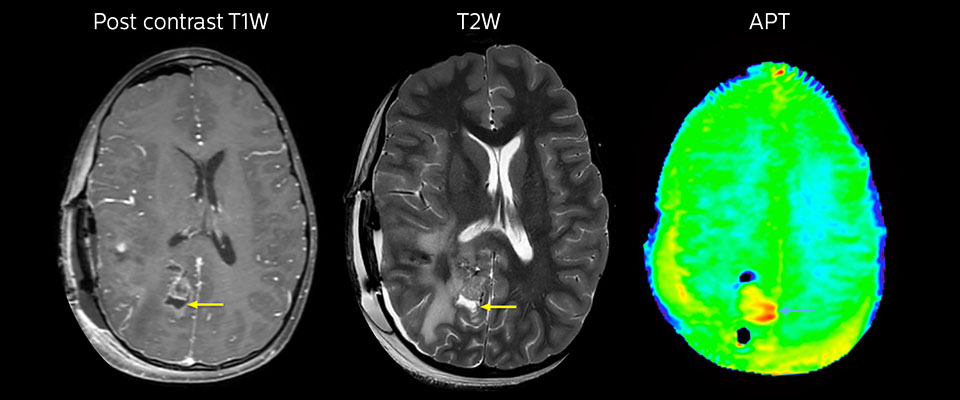

APT in post-surgery evaluation

Large metastatic brain lesion

This 10-year-old patient underwent Ewing’s sarcoma tumor resection 7 years ago, but was found to now have a large metastatic lesion in the brain. This lesion shows clearly increased APT signal.

MRI with APT post resection

Immediately post resection MRI was again performed. T2-weighted and postcontrast T1-weighted images are quite inconclusive for distinguishing residual tumor tissue from postoperative tissue changes. On the APT image some high signal is still seen, which would suggest residual tumor tissue.

Follow-up over time

In later follow-up scans the post-contrast T1-weighted images suggest recurrent tumor growth. So, it would be interesting to study the predictive value of APT in a large patient group.